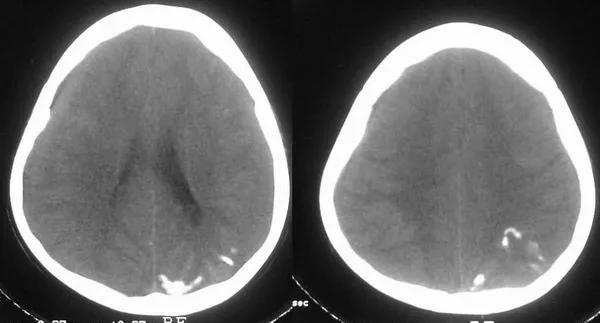

SW综合征全称为斯特齐-韦伯综合征(Sturge-WeberSyndrome),又名脑-三叉神经血管瘤病综合征或脑面血管瘤病综合征,以颜面部、眼部、软脑膜的血管病变为三大表现的血管畸形发育性疾病。其主要表现为:

1、面部三叉神经处大面积鲜红斑痣;

2、智力发育迟缓、智力低下、癫痫;

3、一侧肢体无力或瘫痪;

4、眼部眼压增高或降低,伴有眼球内陷、突眼或眼萎缩;

5、致青光眼或视网膜脱落;

需要注意的是,SW综合征虽伴有智力低下等症状,但在智力迟缓及癫痫发生之前,一般智力发育是正常的,甚至有智力早熟。由于孩子不能自述,导致部分家长错过了治疗时机。目前SW综合征的发病机制尚不清楚,但是笔者和医生都建议,如果在幼儿时期有疑似症状,要及早治疗,防止疾病进一步发展。

对于面部大面积鲜红斑痣患友,尤其是大面积鲜红斑痣位于三叉神经第一支的患友(如上图),建议及早进行核磁共振检查、眼压检查,及早治疗。

2、对于颅脑病变,由神经内外科医生进行专业评估后决定药物治疗或手术治疗;